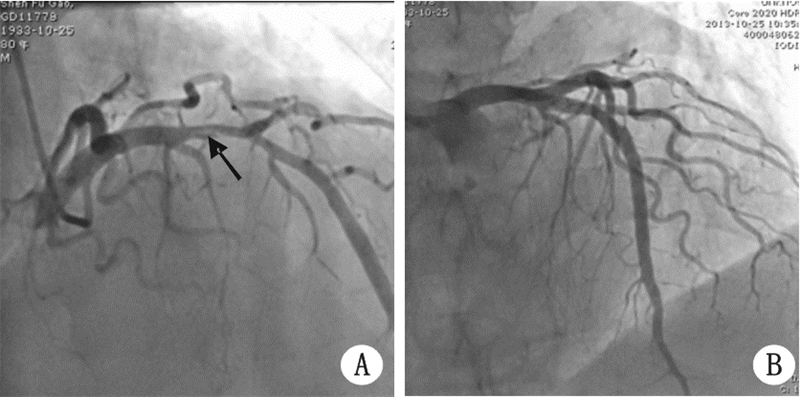

1 资料与方法病例1 患者,男,80岁,因“突发胸闷痛5 d”入院。 2013-10-10休息时突发胸痛,位于胸骨中下段,呈压榨样,约巴掌大小范围,向左上肢及肩背部放射,有濒死感,伴出冷汗,伴恶心、呕吐一次,无黑矇、晕厥,在当地医院就诊,查心电图:急性广泛前壁心肌梗死,予阿司匹林、氯吡格雷抗血小板,低分子肝素抗凝,阿托伐他汀调脂,单硝酸异山梨脂扩冠等治疗。患者于2013-10-14两次出现室速,两次均以100 J电复律后转为窦性心律,后胺碘酮应用,2013-10-15转入本院。既往史:患者有高血压病史十余年,血压最高150/90 mmHg(1 mmHg=0.133 kPa),不监测血压,不服用药物;有2型糖尿病史3年,不监测血糖,不服用药物;否认吸烟史;10年前有外伤性脑出血病史,保守治疗后无后遗症。入院查体:BP 135/85 mmHg,神清,呼吸平,两肺呼吸音清,两肺未及啰音,心率66 次/min,律齐,未及病理性杂音,腹软,无压痛,双下肢无浮肿。快速心肌酶:CK-MB 5.4 ng/mL(正常值0~4.3),TNI 8.03 ng/mL(正常值0~0.4)。入院后心电图:Ⅰ、avL、V3~V6病理性Q波形成(图 1)。BNP 579 pg/mL。床边心超:左室前壁及前侧壁收缩活动减弱,主动脉瓣轻度返流,少量心包积液。诊断:急性广泛前壁心肌梗死,冠心病,阵发性室性心动过速,心功能Killip Ⅰ级,高血压病1级,2型糖尿病。入院后经过抗凝、抗血小板、调脂稳定斑块等治疗,患者病情稳定。于2013-10-25日行冠脉造影显示左前降支近段自发性夹层(图 2A),回旋支、右冠未见明显狭窄。以EXCEL 4.0 mm×18 mm、EXCEL 4.0 mm×24 mm雷帕霉素药物支架植入左前降支近中段病变,两支架部分重叠(图 2B)。术后随访至今,患者无不适主诉。

| 图 1 病例1入院时心电图 A:(箭头示自发性夹层);B:支架植入后冠脉造影结果 |

| 图 2 病例1冠脉造影结果 |